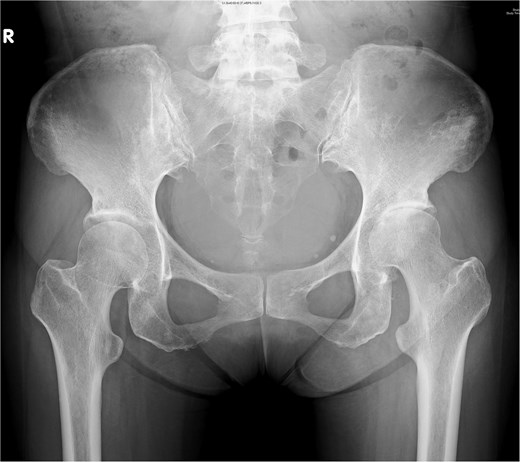

A 44-year-old female, with a medical history of invasive ductal carcinoma of the breast with multiple sites of metastasis (brain, pulmonary, liver, and bone), presented to the outpatient clinic with progressive intractable pain over the left inguinal area in the preceding month. Radiography revealed symmetrical joint space narrowing of the left hip joint (Fig. 1). Computed tomography (CT)revealed a well-lobulated cystic lesion within the left psoas muscle, extending caudally into the hip joint (Fig. 2a and b). The serum C-reactive protein (CRP) level was 55.04 mg/dl at admission. Due to the inaccessibility of CT-guided percutaneous abscess drainage, she underwent a scheduled surgical debridement of the psoas abscess. Resection arthroplasty with polymethylmethacrylate hip spacer implantation was planned simultaneously.

Pelvic radiograph of a 44-year-old female showing symmetric left hip joint space narrowing, indicative of hip septic arthritis.